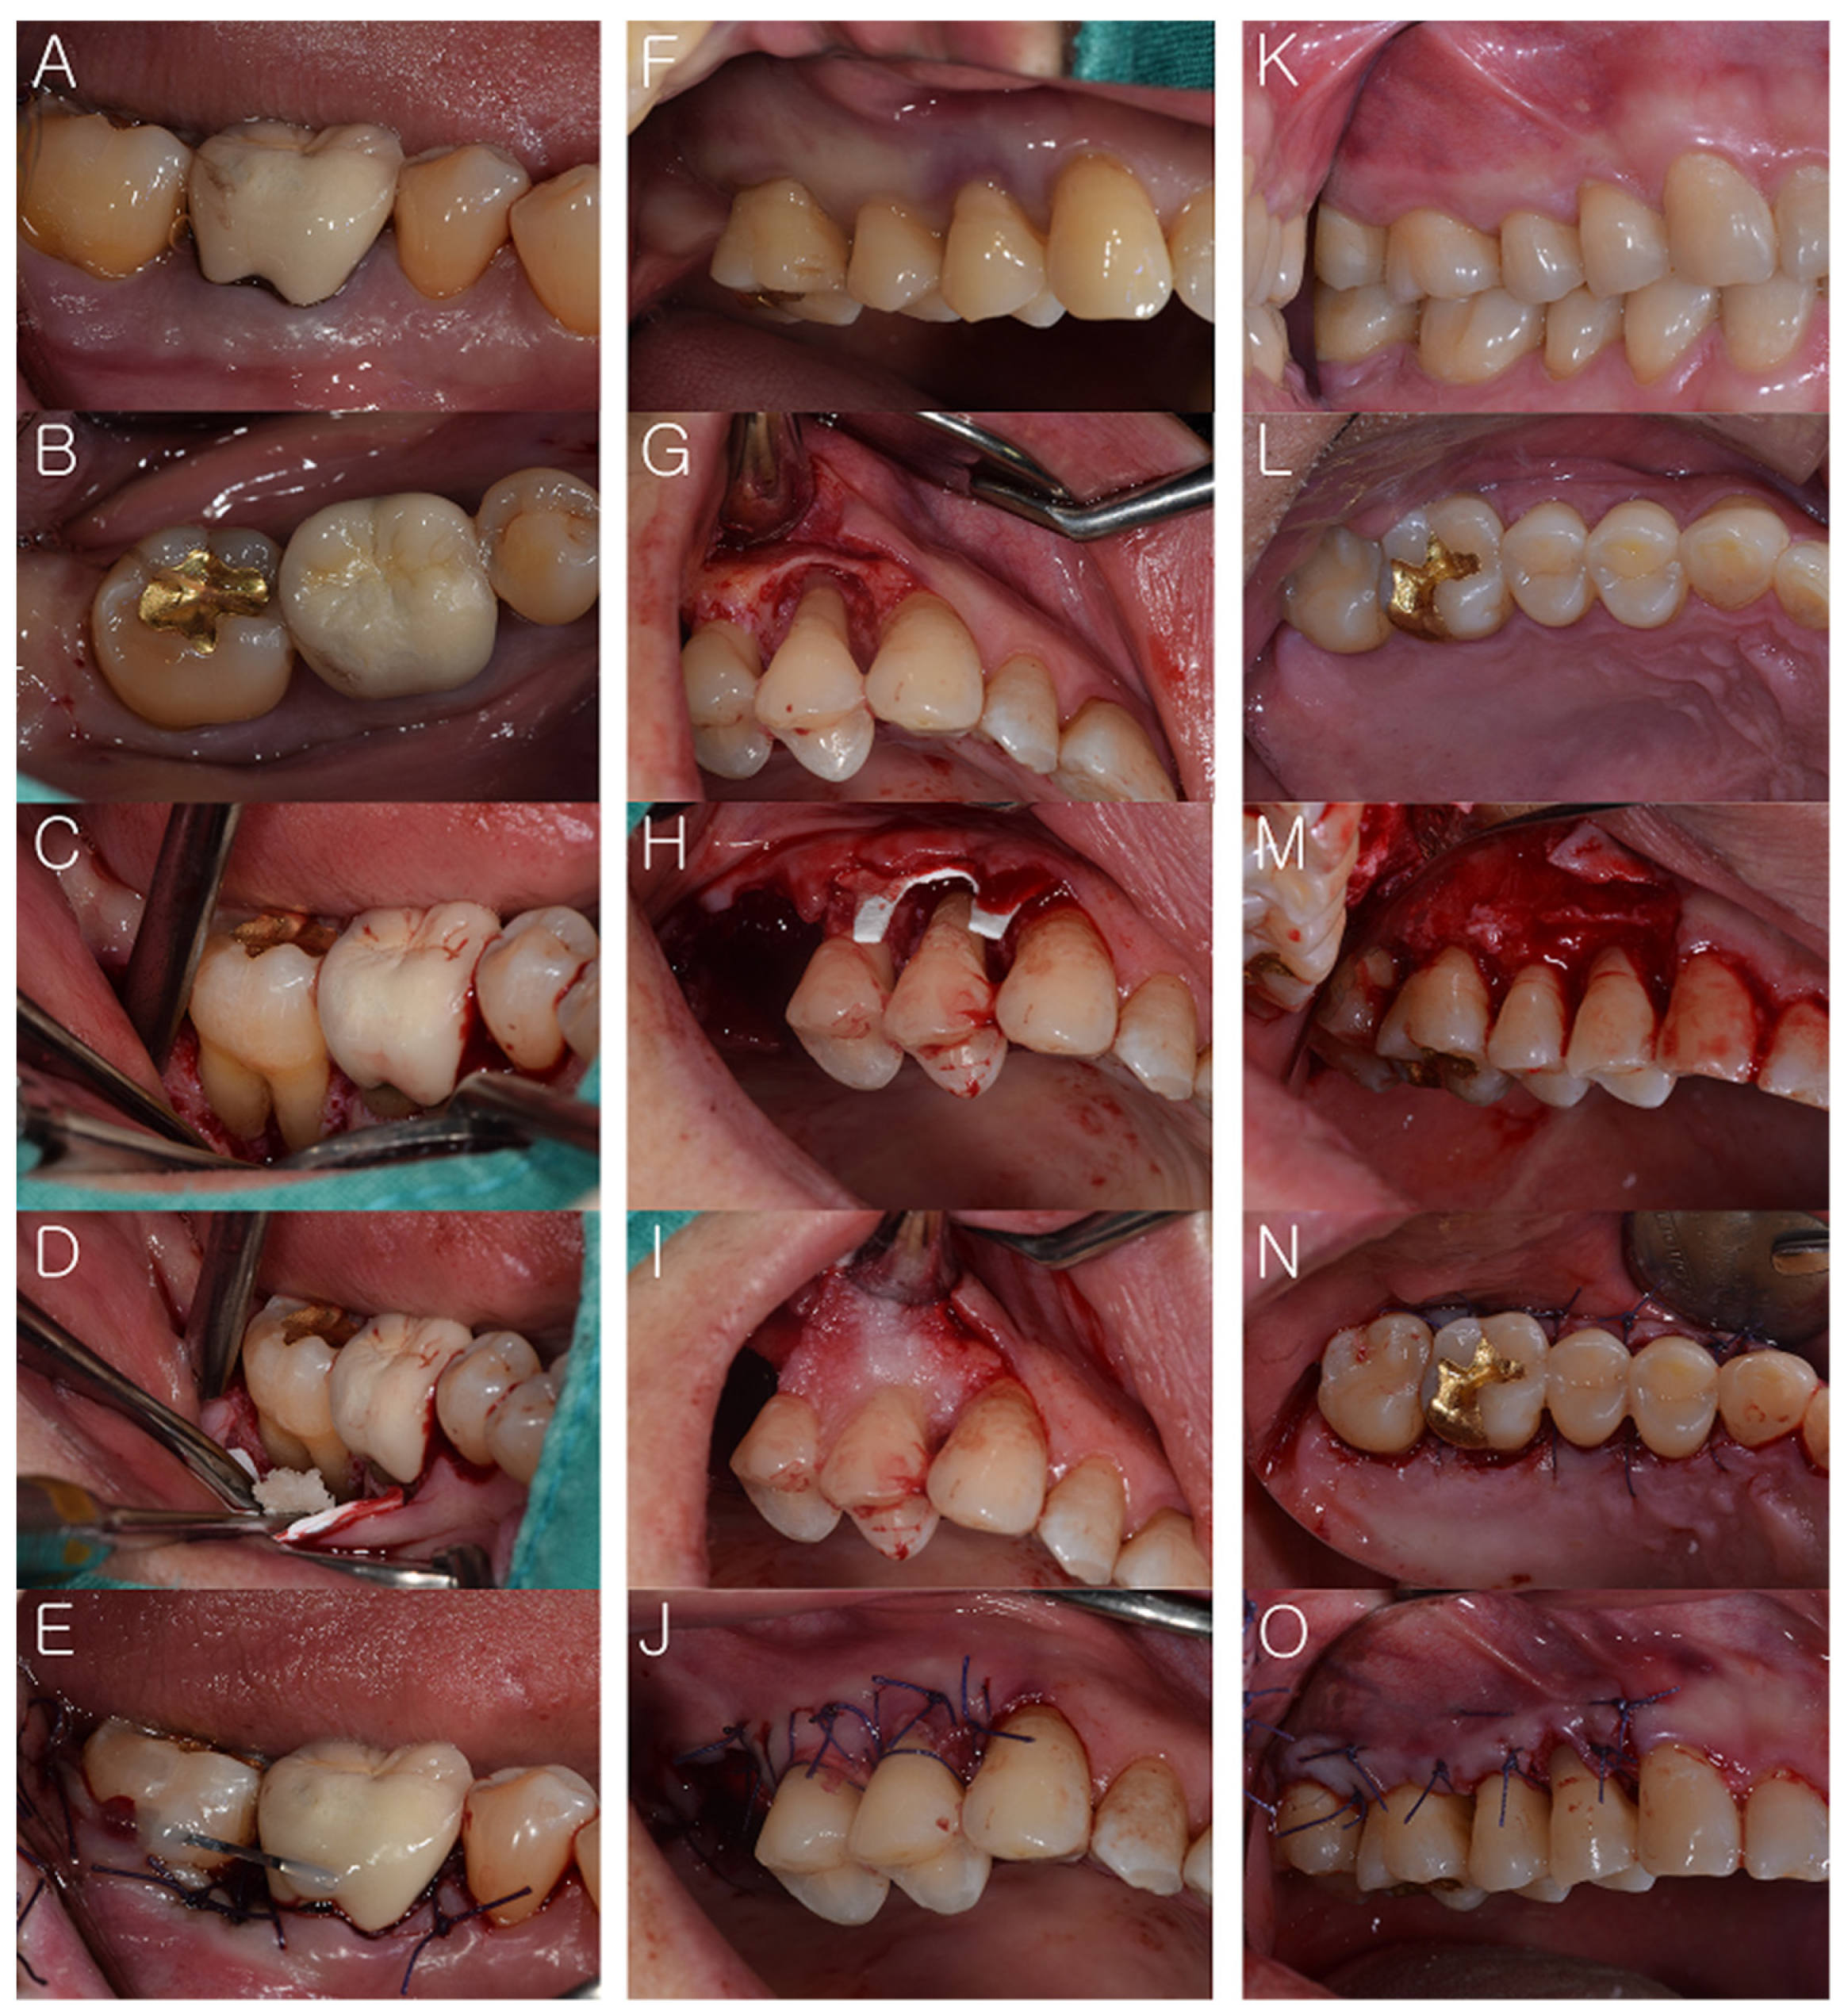

:1. Introduction

2. Materials and Methods

2.3. Surgical Procedures